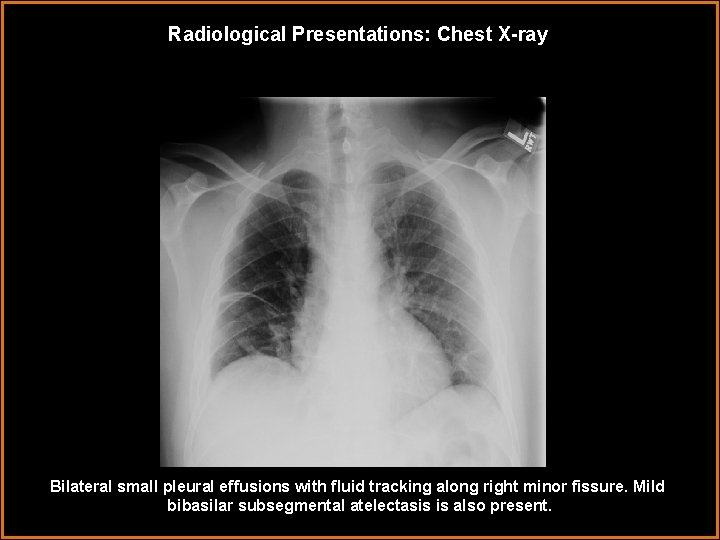

Radiological Presentations: Chest X-ray Bilateral small pleural effusions with fluid tracking along right minor fissure. Mild bibasilar subsegmental atelectasis is also present.

Findings and Differentials Findings: Chest radiograph demonstrates small bilateral pleural effusions with possible intervertebral disc space narrowing and illdefined endplates at one of the levels in the lower thoracic spine. A focal bulge at the lower left para spinal stripe is also visualized which is subtle. CT demonstrates T 8 -9 opposing endplate irregularity and erosive changes with mild pre- and paravertebral soft tissue swelling. MRI findings reveal altered marrow signal with enhancement of T 8 -T 9 vertebrae. Differentials: • Degenerative changes • Osteomyelitis • Vertebral body neoplasm